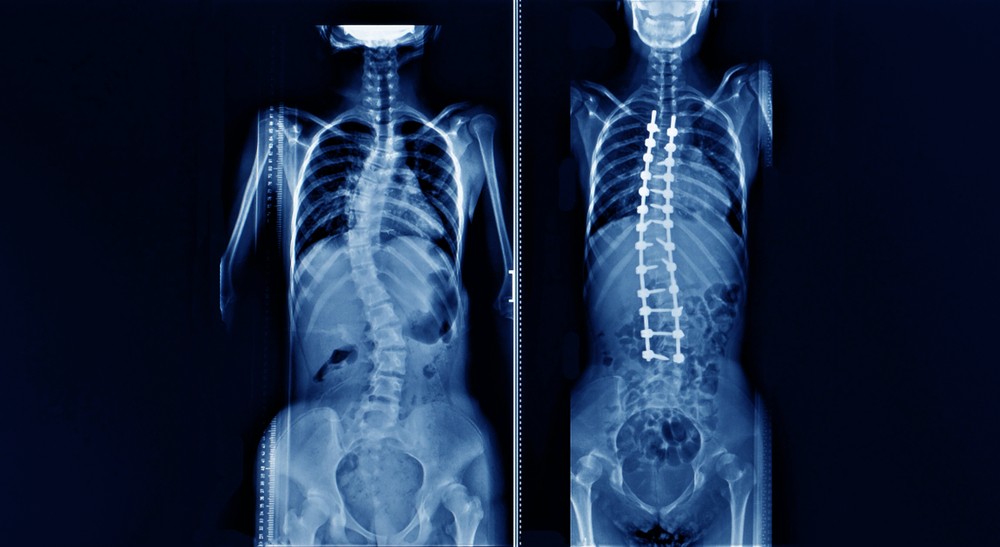

全港10至18歲的兒童及青少年,約有3.5%受到青少年特發性脊柱側彎(AIS)影響。傳統治療方式包括使用外部支架或侵入性融合手術,前者需要時間長,後者則易留下較大手術創口。香港大學李嘉誠醫學院(港大醫學院)矯形及創傷外科學系領導的外科團隊,最近成功完成香港和中國內地首宗通過VBT(Vertebral Body Tethering)技術進行的非融合脊柱側彎手術。

進行是次手術的病人是9歲、趙太的兒子。趙太在2014年發現兒子在寫字時坐得有點歪,經檢查後發現他有脊柱側彎,側彎達到28度。在醫生建議下,配戴了兩年支架,但矯正效果仍然欠佳,趙太兒子在2018年時側彎角度更達45度。醫生認為,趙太的兒子適合做VBT技術進行的非融合脊柱側彎手術。今年2月進行手術過後,趙太兒子的在深切治療部觀察了兩日,精神狀態十分好。手術後一個月,兒子康復進度良好,恢復正常活動,行動也沒有受到限制,亦很快可以上學,暫時未有任何不良影響。

青少年特發性脊柱側彎(AIS)的脊柱會呈現C形或S形,屬於三維畸形。全港10至18歲的兒童和青少年中,約有3.5%人士受此病症影響,其中又以女孩和處於青春期者的發病率更高。未經治療的脊柱側彎,會導致側彎惡化、背痛、心肺功能下降、軀幹失衡等問題,亦會影響外觀及心理發展。傳統上,嚴重的脊柱側彎,是需要通過手術治療:在患者背部切下很長的傷口、剖開肌肉以進行植入治療棒和螺絲釘的融合手術。即使手術成功,也會使脊柱變得僵硬,並限制患者進行某些活動。

手術過程涉及五個鎖孔切口,並透過胸腔鏡(專用相機進入胸腔)清晰地觀察脊柱。剖開脊柱後,在X光射線引導下,從脊柱側面在每節脊椎水平處放入鈦螺絲釘,然後使用非剛性帶VBT連接螺絲釘。該繫鏈可以限制脊柱凸側的生長,同時又讓脊柱在凹側的一方生長;隨著脊柱的生長,脊柱的彎度得以逐漸矯正。

這項手術適用於受中度(40至60度)脊柱側彎影響及正在發育的兒童。過去8年間,該新式手術主要在北美和歐洲的指定醫療機構進行,取得良好效果。港大醫學院是首個在本港引入這項手術的機構,也是大中華區唯一一家完成這項手術的機構。此項新型手術利用患者自身的生長過程,讓脊柱側彎隨著時間生長而逐漸得以矯正。患者無需接受開放性手術,並且避免脊柱因為長期融合而可能導致僵硬、以及相鄰脊椎退化的問題。港大醫學院矯形及創傷外科學系系主任張文智教授表示:「這項新手術開展了脊柱側彎手術治療的新時代。兒童可以正常活動,不再受支架帶來的心理負擔或長期融合手術的影響。」